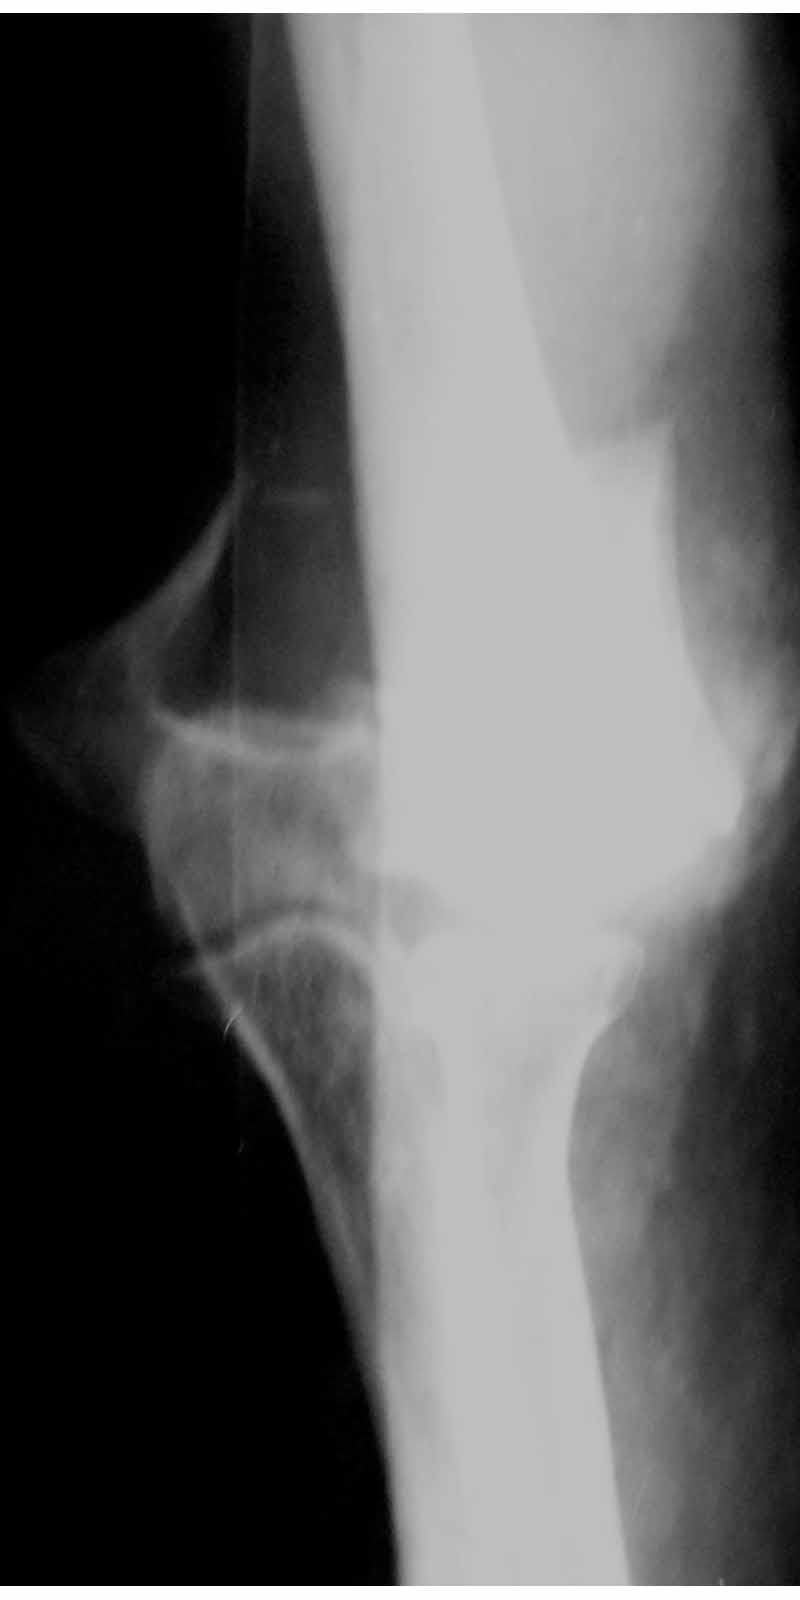

Солидарен с мнением обоих Александров (Челнокова и Рыкова): точную репозицию такого перелома вряд ли удастся выполнить закрыто. Даже во время открытого вмешательства это сделать непросто. Неслучайно предложен костно-пластический доступ с временным отсечением локтевого отростка. И по методу фиксации согласен с Александром Челноковым: 2 пластины. В качестве примера привожу рентгенограммы одного из наших пациентов с аналогичным повреждением.

С уважением, А. Золотов, Приморский край.

Alexander Artemiev 14 Сентябрь 2005, 16:19

Снимки - во вложении.

Женщина 42 лет, операция через неделю после перелома.

Д-з - открытый перелом мыщелков со смещзением и локтевой кости

без смещения - падение с лошади.

Остеосинтез закрытый (если так можно выразиться), т.е. без

разрезов. Длительность операции - около 1,5 часа со студентом.

6 щелчков ЭОПом.